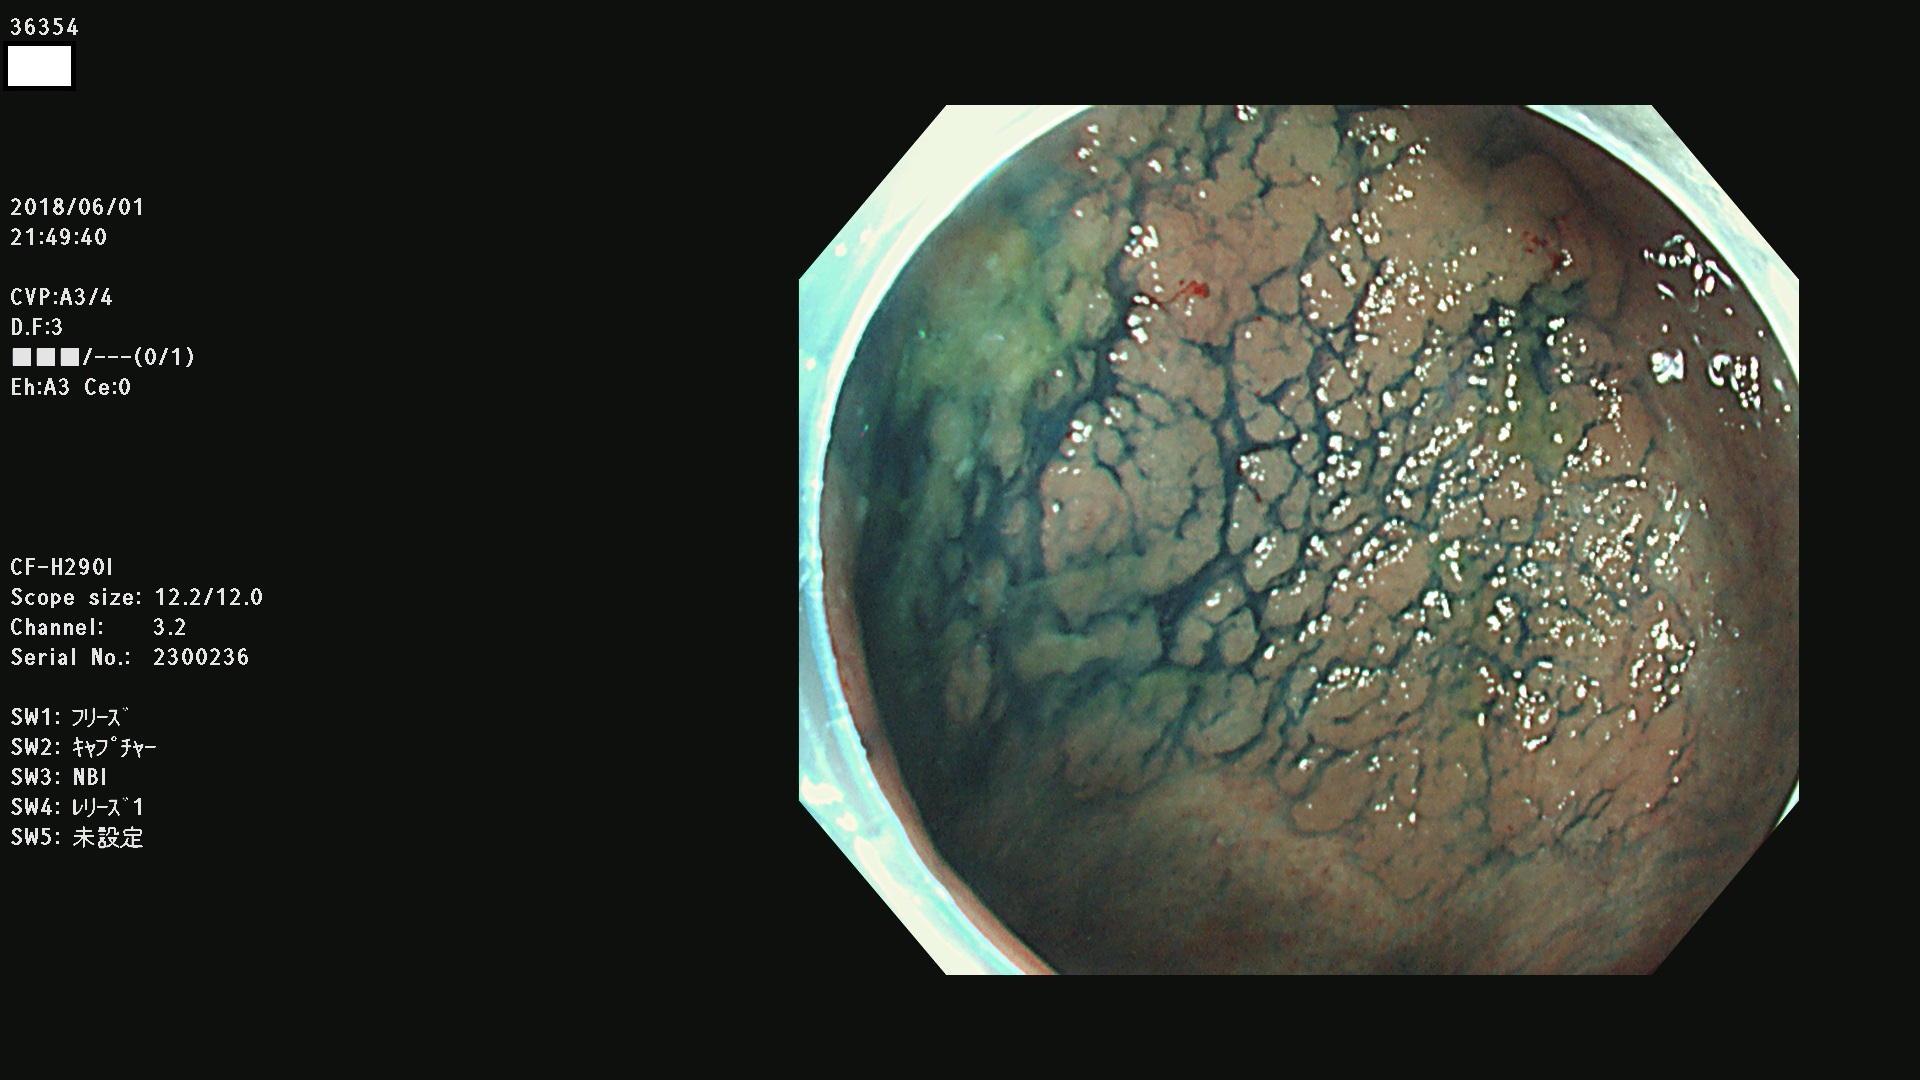

腺腫発見率 68 % (カルテ番号 36300〜36399の100名の方の検査結果で集計)大腸癌検診最新情報

以下のカルテ番号の方に腺腫(Adenoma,Group3〜5)が見つかりました(集計法)

36300 36302 36305 36306 36307 36308 36310 36311 36312 36313 36314 36315 36316 36318 36321 36322 36324 36325 36326 36327 36330 36332 36333 36334 36335(SSAPのみ) 36337 36338 36339(SSAPのみ) 36340 36341 36342(SSAPのみ) 36343 36344 36346 36348 36349 36351 36353 36354 36355(SSAPのみ) 36356 36357 36358 36359 36364 36365 36366 36367 36370 36374 36376 36379 36381 36382 36383 36384 36385 36387 36388 36389 36390 36392 36393 36395 36396 36398 36399

発見困難で危険性の高い平坦型病変(上記100名より抽出) ![]()